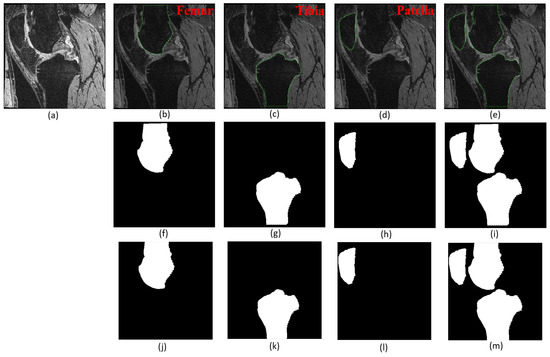

3.2.2. Segmentation Performance